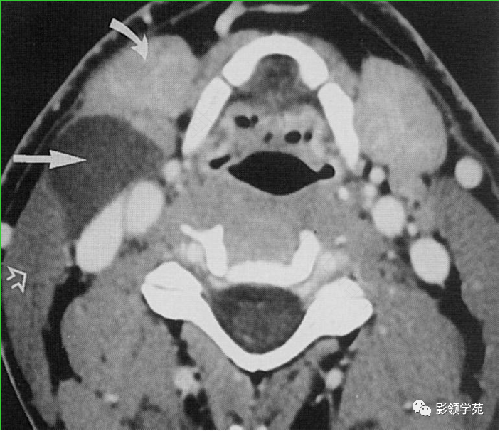

囊性占位病变就是指病发部位出现囊肿或包裹性积液也称之为囊性肿瘤。但是囊性占位病变是良性的,并不是癌症。通过超声、核磁共振或CT都能检查出来,常见的囊性占位病变有卵巢囊肿或双管积液。不管是哪个部位的囊性占位病变,都需要去医院进行治疗。而且在治疗期和恢复期也要定期去检查,因为这类疾病的复发率很高。